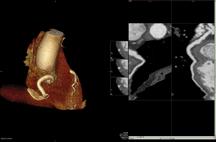

Using the Vantage Atlas MR system, Dr. Albert diagnosed a large heart attack affecting the lateral wall, but live (viable) territory in the area which caused concern for ischemia.

Vantage Atlas MR

The CVDC uses Toshiba’s Vantage Atlas MR system for cardiovascular imaging without exposure to X-ray radiation. Similar to the Aquilion ONE, MR shows both anatomy and function, such as blood flow. It is used in imaging valve structure, heart function, heart attack patients and when there is heart failure for unclear reasons.

“Prior to the inception of the CVDC, advanced cardiovascular MR imaging was generally limited to academic centers,” explained Dr. Albert. “Cardiac MR has revolutionized the way we look at the heart as it creates movie-quality images, similar to the difference between black and white television versus today’s high-definition television. MR also completely eliminates radiation dose, making it a safer option for patients.”